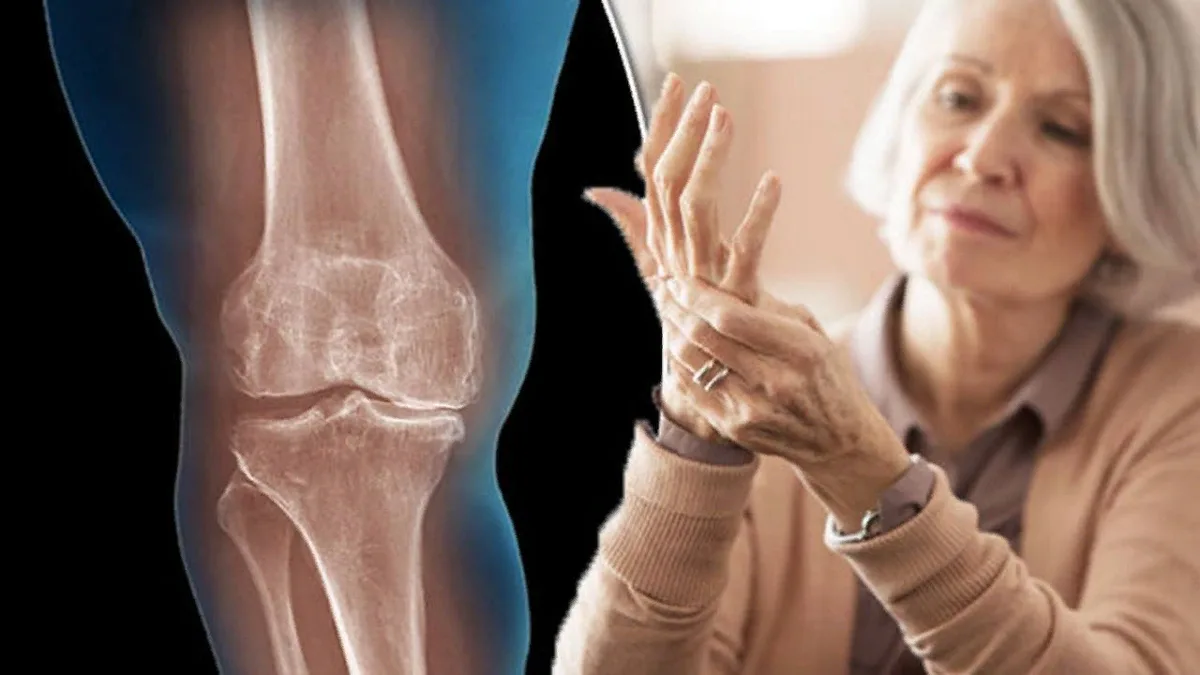

Остеоартрит – это одно из самых распространенных заболеваний суставов, которое приводит к боли, снижению подвижности и ухудшению качества жизни. Это хроническое заболевание, которое может развиваться в любом суставе, чаще всего в коленях, бедрах и руках. В этой статье мы рассмотрим основные методы диагностики и лечения остеоартрита, включая медикаменты и физиотерапию.

Остеоартрит характеризуется дегенеративными изменениями в хрящевой ткани суставов, что приводит к их износу. Основные факторы риска включают:

- Возраст: С возрастом риск развития остеоартрита увеличивается.

- Избыточный вес: Лишний вес создает дополнительную нагрузку на суставы.

- Травмы: Повреждения суставов могут способствовать развитию остеоартрита.

- Генетическая предрасположенность: Наличие остеоартрита у близких родственников может увеличить риск заболевания.